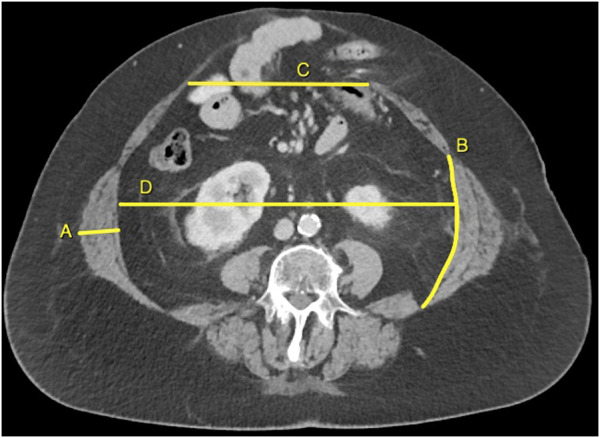

Background: Intramuscular injection of botulinum toxin A (BTA) induces a temporary muscle paralysis. In patients with a ventral hernia, preoperative injection of BTA in the muscles of the lateral abdominal wall (LAW) leads to thinning and lengthening of these muscles, making fascial closure more likely. In many hernia centres, treatment with BTA prior to abdominal wall reconstruction has therefore become standard care. However, evidence on the optimal BTA strategy is lacking. Methods: In this single-centre retrospective study, we analysed a consecutive cohort of ventral hernia patients that underwent bilateral BTA injections prior to abdominal wall reconstruction with available CT before and after BTA. We only included patients that were treated with exactly 600 units of Dysport®, diluted into 120 mL of saline, via either two- or three injections on each side into all three LAW muscle layers. The primary outcome was the change in LAW muscle length and thickness, comparing CT measures from before BTA and 4-6 weeks after the injections. Results: We analysed 67 patients; 30 had received two injections bilaterally and 37 had received three injections bilaterally. Baseline data showed no significant differences in LAW muscle thickness or length between groups. In both groups, the median LAW muscle thickness decreased with 0.5 cm (p < 0.001). The LAW muscle length increased with 0.9 cm (p = 0.001) and 1.2 cm (p < 0.001) in the two- and three bilateral injection group, respectively. The BTA-induced changes in LAW thickness and length were not significantly different between both groups (p = 0.809 and p = 0.654, respectively). Discussion: When using the exact same dosage and distribution volume of BTA in patients with a complex abdominal wall defect, two injections bilaterally in the lateral abdominal wall muscles are as effective as three injections bilaterally.